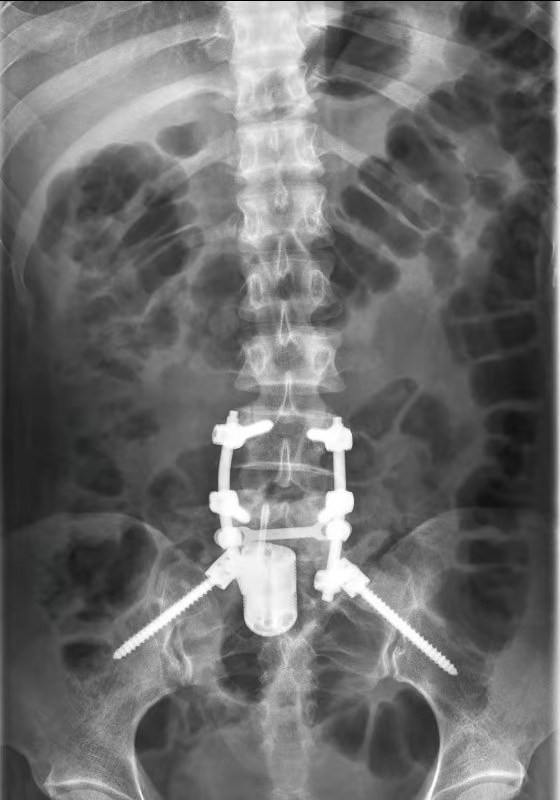

面对如此巨大的挑战,韩学哲、边卫国团队凭借多年对骨肿瘤疾病治疗的经验体会,特别是脊柱肿瘤手术技术的沉淀和积累,制定了个体化的手术方案---先俯卧位进行后路手术,切除骶1椎体附件及所有连接结构,充分减压并进行椎弓根螺钉内固定术,再翻身仰卧位经腹部入路整体切除骶1椎体,并植入3D打印人工椎体。手术当日,在麻醉手术部和骨科专业组的密切配合下,手术得以成功实施。

由于肿瘤组织与硬膜囊和右侧骶1神经根紧紧相邻,后路完整切除肿瘤及椎体附件的困难极大。凭借过硬的手术技术,韩学哲、边卫国教授完整地分离出骶神经和硬膜囊并将椎体附件完整切除。后路手术顺利完成后,在手麻部门的密切配合下,将患者翻身经腹部行前路手术。经腹腔入路手术对于骨科医生来说是相对陌生的手术入路方式,但凭借多年来多学科合作腹部肿瘤切除的丰富经验,团队决定采取脐下正中入路,逐层深入,保护好腹腔内肠管、子宫、膀胱、输尿管等器官,切开腹膜后直达骶1椎体前方。该区域被髂总及髂内动静脉及多根主要神经覆盖,操作难度极大。团队先仔细分离并保护双侧髂血管、骶1神经根前支等神经血管。确认安全操作空间后,将肿瘤连同累及的周围组织,从后至前360度完整切除,最后置入人工椎体。手术历时7小时40分钟,出血400ml,术中未医源性损伤或结扎任何大神经和血管,术后安全返回病房。